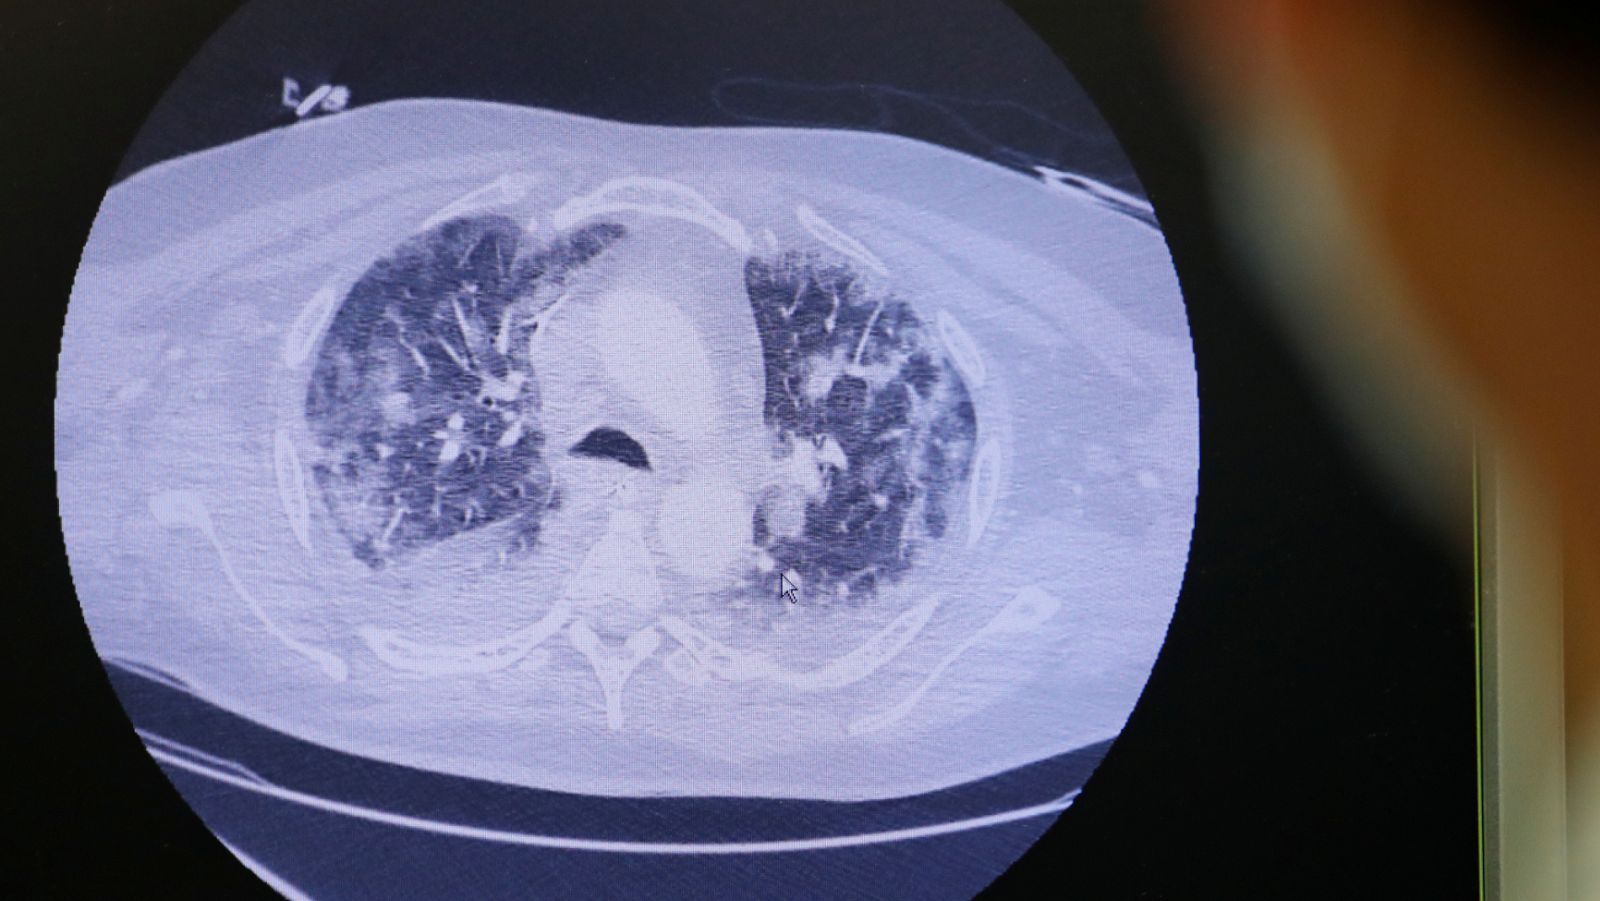

En Francia revisan pruebas que podrían indicar que ya hubo casos de coronavirus a mediados de noviembre

La OMS ha pedido a los países que revisen las historias médicas de pacientes para determinar cuándo empezaron los primeros casos de coronavirus....